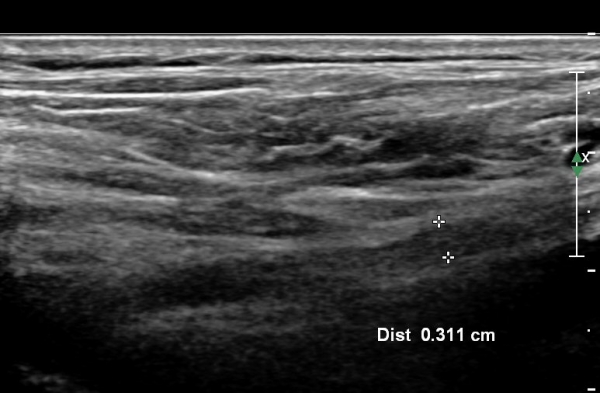

¸ñ ¾Õ ¿ÜÃø¿¡¼­ Á¦5, 6 ½Å°æ±Ù Á¾´Ü¸é°Ë»ç¿¡¼­ Á¦5, 6 ½Å°æ±ÙÀÇ Àú¿¡ÄÚ ºÎÁ¾(4,5mm, 6.5 mm)ÀÌ

°üÂûµÇ°í »çÁø 4,5 ) °ÇÃø(»çÁø 6, 7)(2.4mm, 3.1mm)°ú ºñ±³ÇÏ¸é ¾à 2¹èÀÌ»ó ºÎÁ¾ÀÌ ¶Ñ·ÇÇÔ.